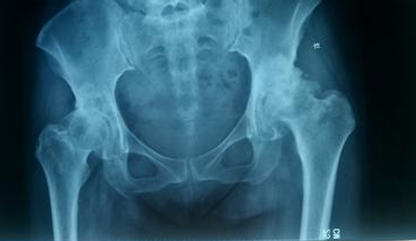

1、退变性髋关节骨性关节炎是人工髋关节置换术的首选适应征

2、股骨头缺血性坏死是此项手术的常见病及多发病

3、高龄患者的股骨颈骨折

4、创伤性骨关节炎

5、类风湿性关节炎及直性脊柱炎

6、良性和恶性骨肿瘤

总之,只要有关节破坏的X线征象,伴有中度至重度持续性的关节疼痛和功能障碍,而且通过其他各种非手术治疗都不能得到缓解的疾病,都有进行关节置换手的指征。